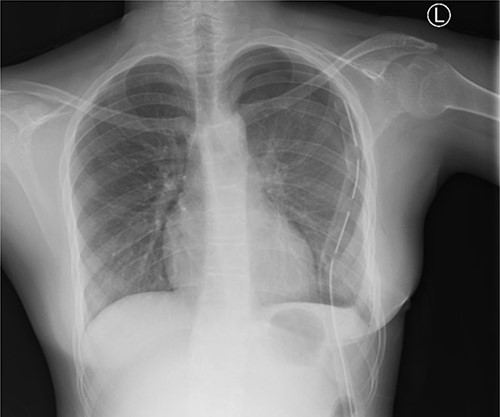

An initial chest radiograph of the patient confirmed tracheal deviation and revealed a mass in the left hemithorax. Chest CT scan (Fig. 1) showed a large mass occupying the entire left posterior hemithorax measuring 12.3 cm (AP) × 14.4 cm (T) × 22.8 cm (CC) with associated partial collapse of the left lung and mediastinal shift to the contralateral side suggestive of pleuropulmonary blastoma vs. neurogenic tumor (ganglioneuroma). This was followed by a CT-guided core needle biopsy which revealed benign spindle cells on a myxoid background. Abdominopelvic ultrasound was normal.

Chest X-ray (PA) shows no mass in the left hemithorax after thoracotomy and tumor resection; chest tube in situ; heart and lungs appear normal.